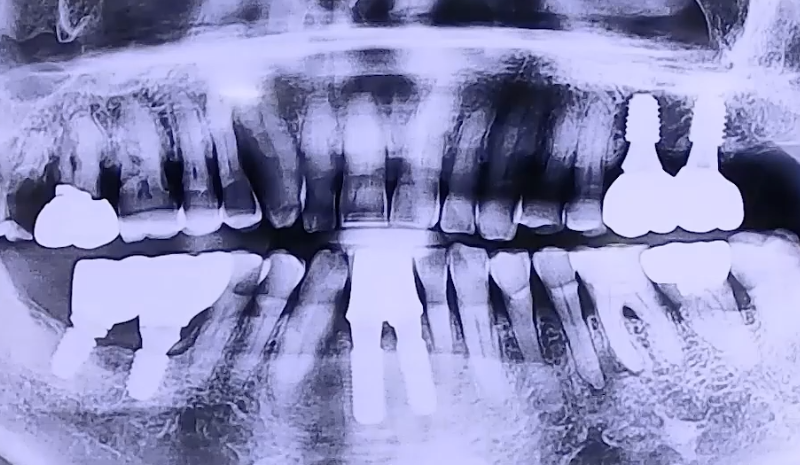

AFTER

좌우 골고루 치아를 사용하실 수 있도록 오른쪽 아래 어금니, 왼쪽 위 어금니에

임플란트 치료를 진행하시고, 약해졌던 앞니도 얇은 임플란트로 치료해 드렸습니다.